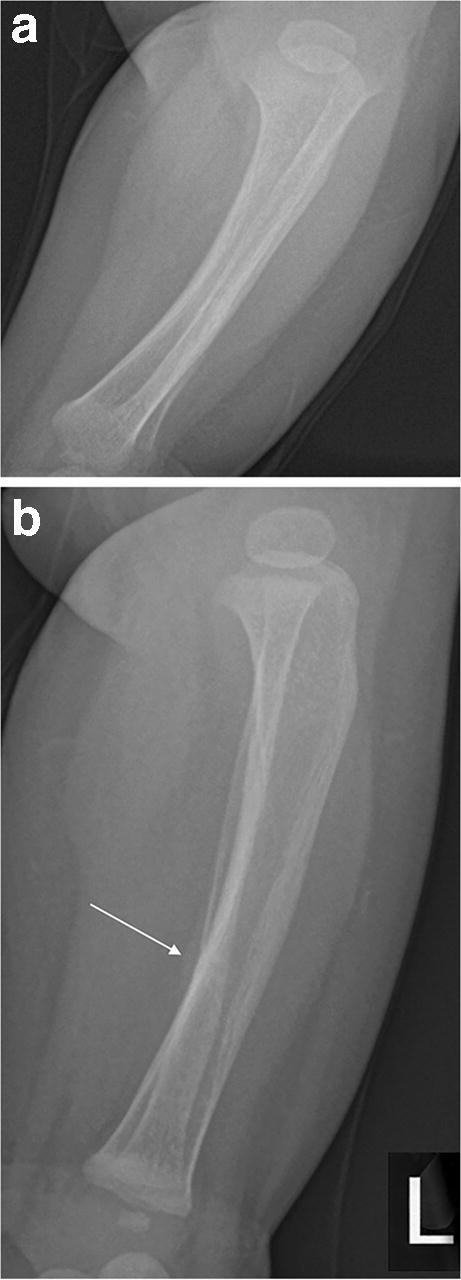

Fig. 1.

A 6-month-old boy with healing fractures of both fibulae. a–b Anteroposterior (a) and lateral (b) radiographs (cropped and magnified) of the left tibia and fibula. There is subtle periosteal reaction along the posterior cortex of the fibular shaft at the junction of middle and distal thirds (arrow). A faint horizontal line runs through the posterior cortex of the fibula, centred on the periosteal reaction and suggests an undisplaced fracture. Images were initially reported as normal